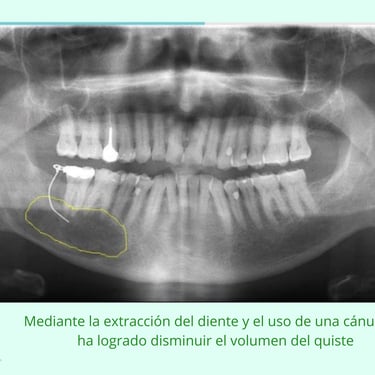

El cirujano evalúa el tamaño y ubicación del quiste en el maxilar. La descompresión es una técnica que permite reducir el tamaño del quiste antes de una cirugía completa para su eliminación.

Resultados esperados: Reducción del tamaño del quiste, facilitando una cirugía más sencilla y menos invasiva posteriormente.